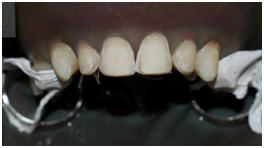

The patient underwent gingivectomy to re-establish the correct position of the gingival collars mainly the zeniths as well as the appropriate clinical length/width ratio of the six anterior teeth (Figure 2).

Figure 2 the gingivectomy from tooth #13 to tooth #23.